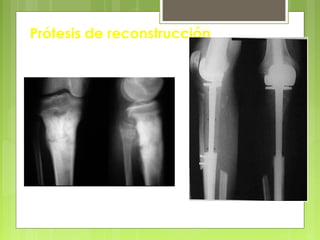

Cirugía

- Amputación

- Resección y reconstrucción

(por medio de prótesis)

- Resección y

reconstrucción

(por prótesis)

Osteosarcoma

Tumores malignos: cirugía de exéresis y de

Osteosarcoma Mujer de 25 años

La resección se debe realizar a distancia de la lesión

Prótesis de reconstrucción